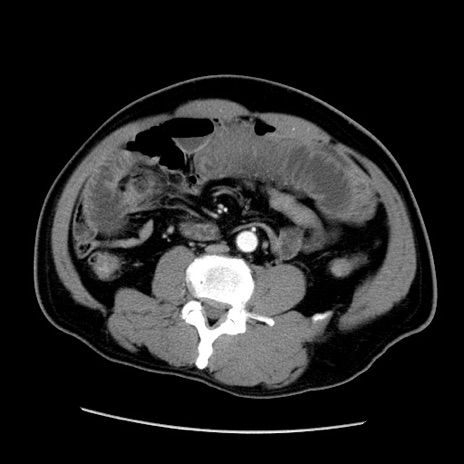

症例22(横断像)

【症例】50歳代男性

【主訴】腹痛

【現病歴】AVMからの被殻出血のため回復期リハ病棟入院中。 本日午後3時頃急に下腹部痛が出現した。

【既往歴】AVM、被殻出血、虫垂炎、高血圧

【身体所見】意識晴明、左半身不全麻痺、会話の理解は良好、36.5°C、腹部:膨隆、全体に板状硬、下腹部正中に圧痛点あり、反跳痛-、筋性防御不明、右下腹部にope scar

【データ】WBC 9400、CRP 0.06